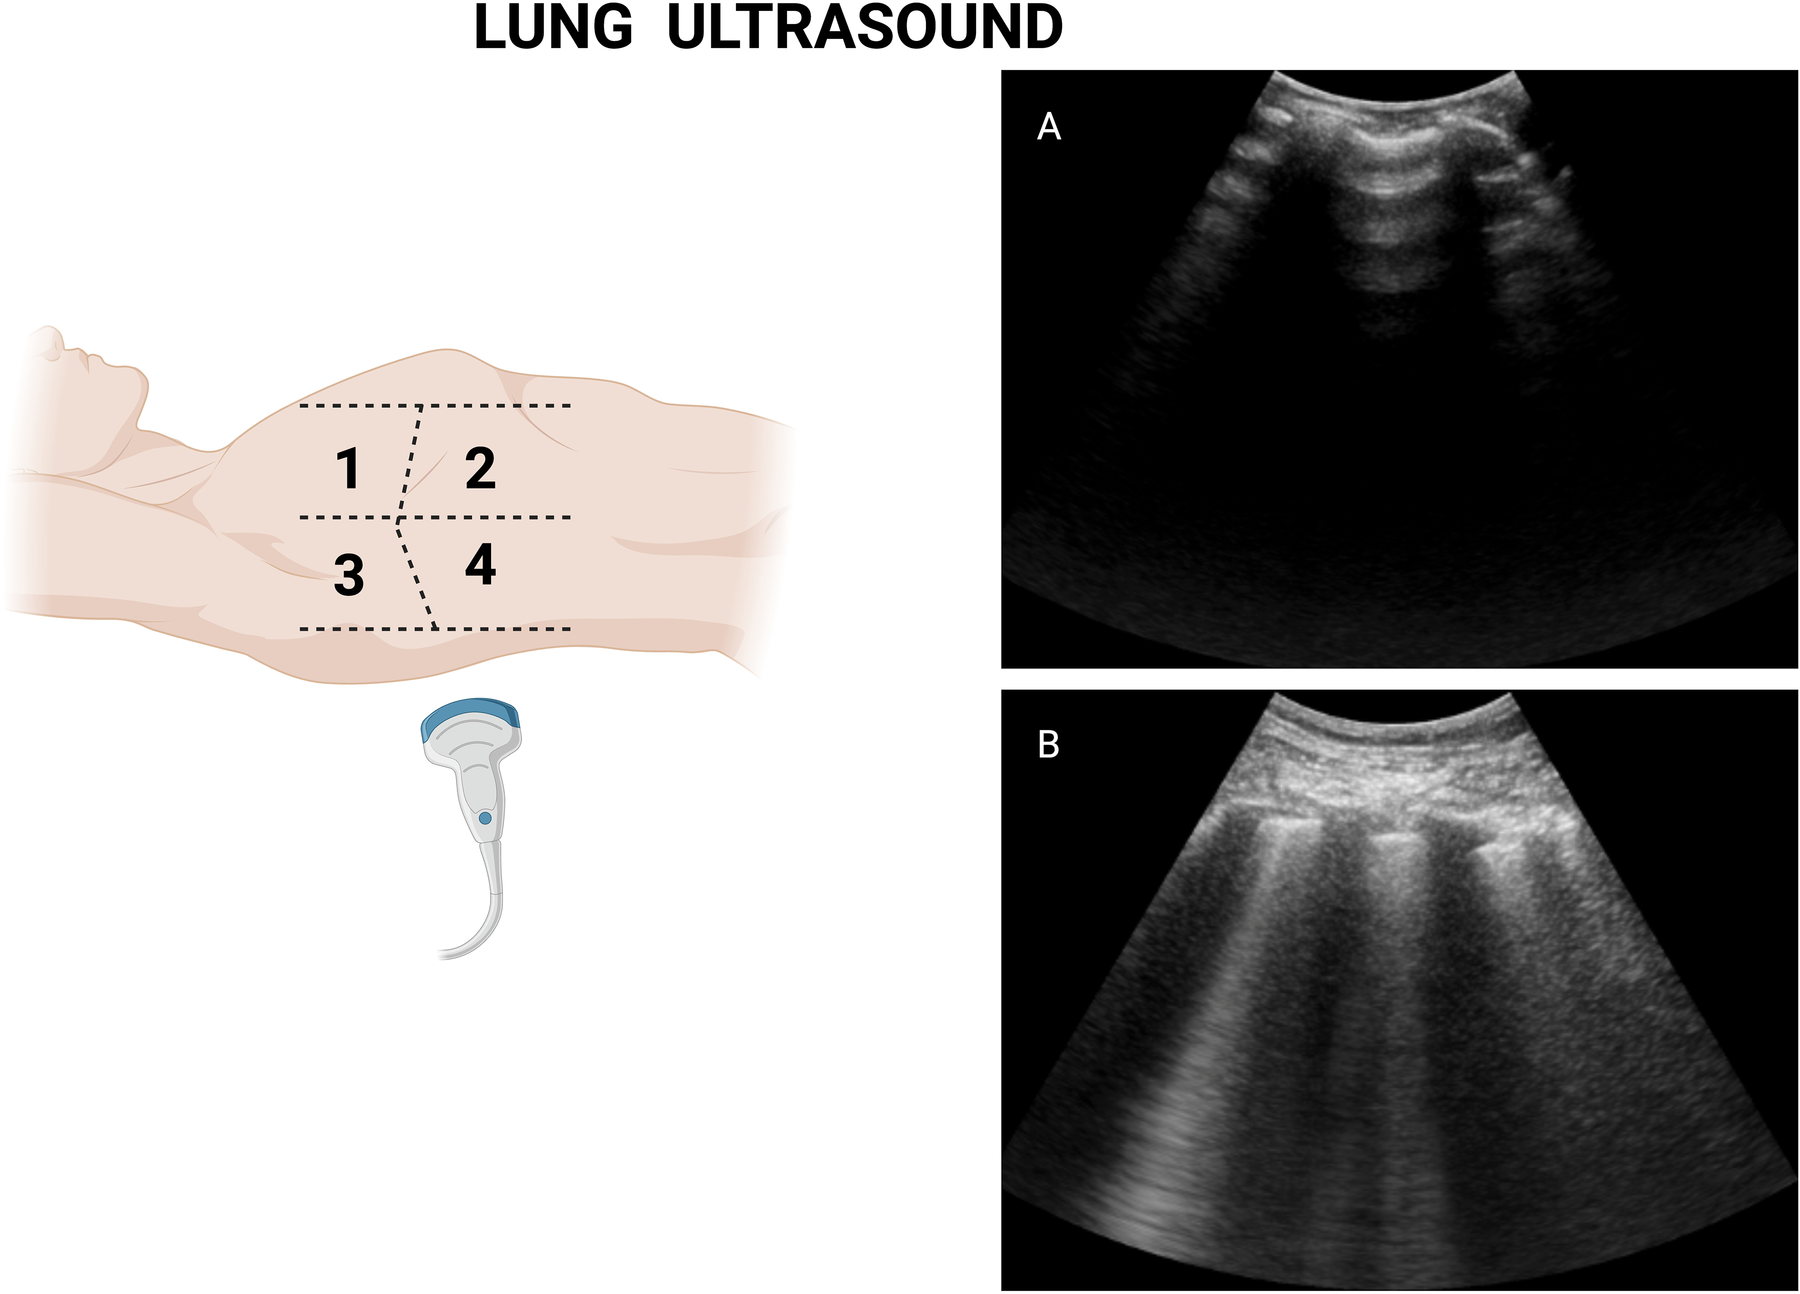

Figure 2

Lung ultrasound measurement illustration. (A) Normal lung with air-filled alveoli. (B) Congested lung with multiple B-lines (comet tail appearance). Figure created in Biorender.com.

Lung ultrasound provides a direct, real-time visualization of extravascular lung water through the detection of B-lines—vertical, hyperechoic artifacts arising from the pleural line and moving with respiration. These artifacts reflect increased fluid within the interlobular septa and alveolar interstitium, making them a sensitive marker of pulmonary congestion, defined as at least two positive sites (≥3 B-lines each) bilaterally (25). Studies have demonstrated that LUS is superior to both auscultation and chest radiography in detecting pulmonary edema, with diagnostic accuracies exceeding 90% in many acute care settings (26). It is important to emphasize that, although a single positive zone does not strictly define pulmonary congestion, its presence may still carry prognostic implications, as will be discussed below. Therefore, for this review, we will define “pulmonary congestion” as the presence of one or more lung zones demonstrating three or more B-lines.

In the context of STEMI, LUS can be performed rapidly at the bedside, typically within a few minutes using an 8-zone scanning protocol (25) (Figure 2). Importantly, the identification of B-lines does not require advanced ultrasound training, as interobserver agreement among trained clinicians is high (30, 31), and it is suggested that one morning of hands-on experience or even a standardized internet-based module of two hours is enough to achieve excellent reproducibility in the identification and quantification of B-lines (24). Of note, both curvilinear and phased array transducers may be recommended for LUS assessment, as there is a good correlation among users who had at least one month of POCUS training (32). The use of the sectorial transducer may be unfamiliar to non-cardiologists or doctors who are not as experienced with this type of transducer. However, an interesting analysis by Walsh (32) and colleagues compared both transducers for lung ultrasound assessment and found a good correlation among trained users.